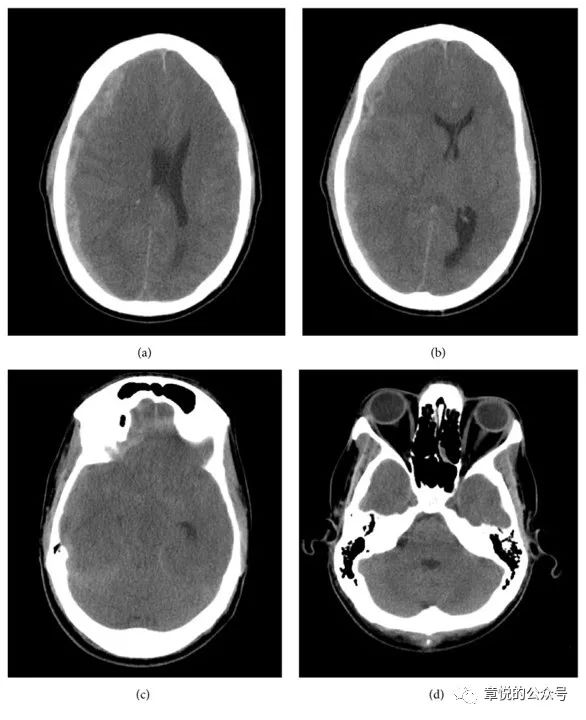

我今天讲述的这例慢性硬膜下血肿由急性者迁延所致,3个月来血肿没有大变化(图1),然而临床症状却突然加重了。

图1. 患者3个月来硬膜下血肿始终没有吸收,1个月前血肿影密度较前增高。

患者老年男性,3个月车祸头部受伤,当时除头痛没有其他症状,到当地医院行CT见左侧硬膜下血肿,因出血量不大,所以神经外科建议保守治疗,3个月中患者几次CT未见血肿吸收,但也没觉得什么不适。1周前患者开始出现头晕和左侧头痛,之后逐步出现意识混乱,言不达意,在入院前2天出现癫痫频繁发作,一天发作几十次,但头颅CT上血肿量并无增多,神经外科仍建议继续保守治疗。